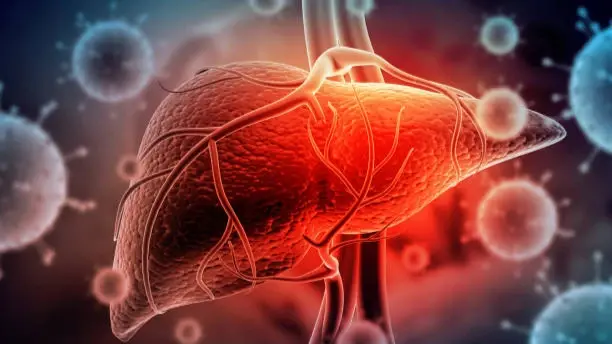

Употребление избыточного алкоголя может привести к разрыву некоторых тканей печени, которые выделяются в виде кровавых следов в вашем стуле.

В то время как связанное с алкоголем заболевание печени обычно не вызывает многих симптомов до тех пор, пока ваша печень не станет «сильно поврежденной», есть некоторые признаки, которые следует заметить. Эксперт рассказывает, что один предупреждающий знак появляется, когда вы идете в туалет. Вот как это определить.

Связанное с алкоголем заболевание печени, или сокращенно ARLD, описывает состояние, вызванное чрезмерным алкоголя. Существует три основных стадии этого состояния, которые различаются по степени тяжести и симптомам. Один признак, который может вызвать тревогу, возникает, когда вы выбираете номер два, пишет express.co.uk.

Хотя ARLD обычно выявляется только во время теста на другой диагноз, это состояние может проявляться некоторыми симптомами.

По словам Моники Вассерманн, медицинского директора Olio Lusso , кровь в стуле может быть признаком этого состояния.

Она сказала: «Употребление избыточного алкоголя может привести к разрыву некоторых тканей печени, которые выделяются в виде кровавых следов в вашем стуле.

«Чрезмерное употребление алкоголя со временем ухудшает нормальное функционирование и структуру печени.

«Алкоголь может вызвать повреждение печени, ослабив кровеносные сосуды, особенно вены в желудочно-кишечном тракте.

«Это ослабляет, воспаляет кровеносные сосуды и делает их более чувствительными, повышая риск внутреннего кровотечения, характеризующегося наличием крови в фекалиях или стуле.

«Печеночная недостаточность также может способствовать кровавому стулу».

Как возникает алкогольное заболевание печени

Печень — один из самых сложных органов в организме, способный фильтровать токсины, регулировать уровень холестерина и сахара в крови, способствовать пищеварению и бороться с инфекциями.

Каждый раз, когда вашей печени приходится фильтровать алкоголь, некоторые ее клетки умирают. Однако он может создавать новые.

Хотя «устойчивый» орган способен восстанавливаться, чрезмерное употребление алкоголя может снизить эту способность.

«Это может привести к серьезному и необратимому повреждению вашей печени», — отмечает NHS.